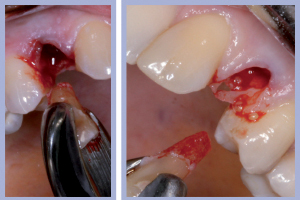

- Figg. 4a, b – Scollamento

- Figg. 5a, b – Estrazione dei canini da latte

- Figg. 6a, b – Estrazione dei canini da latte